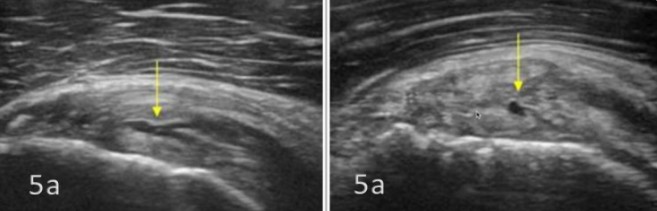

Ejemplo de rotura articular del tendón subescapular:

- Imagen ecográfica superior (no patológica). Las flechas de la imagen superior señalan los fascículos tendinosos hiperecoicos del subescapular, visibles entre las fibras musculares hipoecoicas.

- Imagen ecográfica inferior (patológica). La flecha señala una rotura parcial de la cara articular en la porción superior del tendón subescapular.